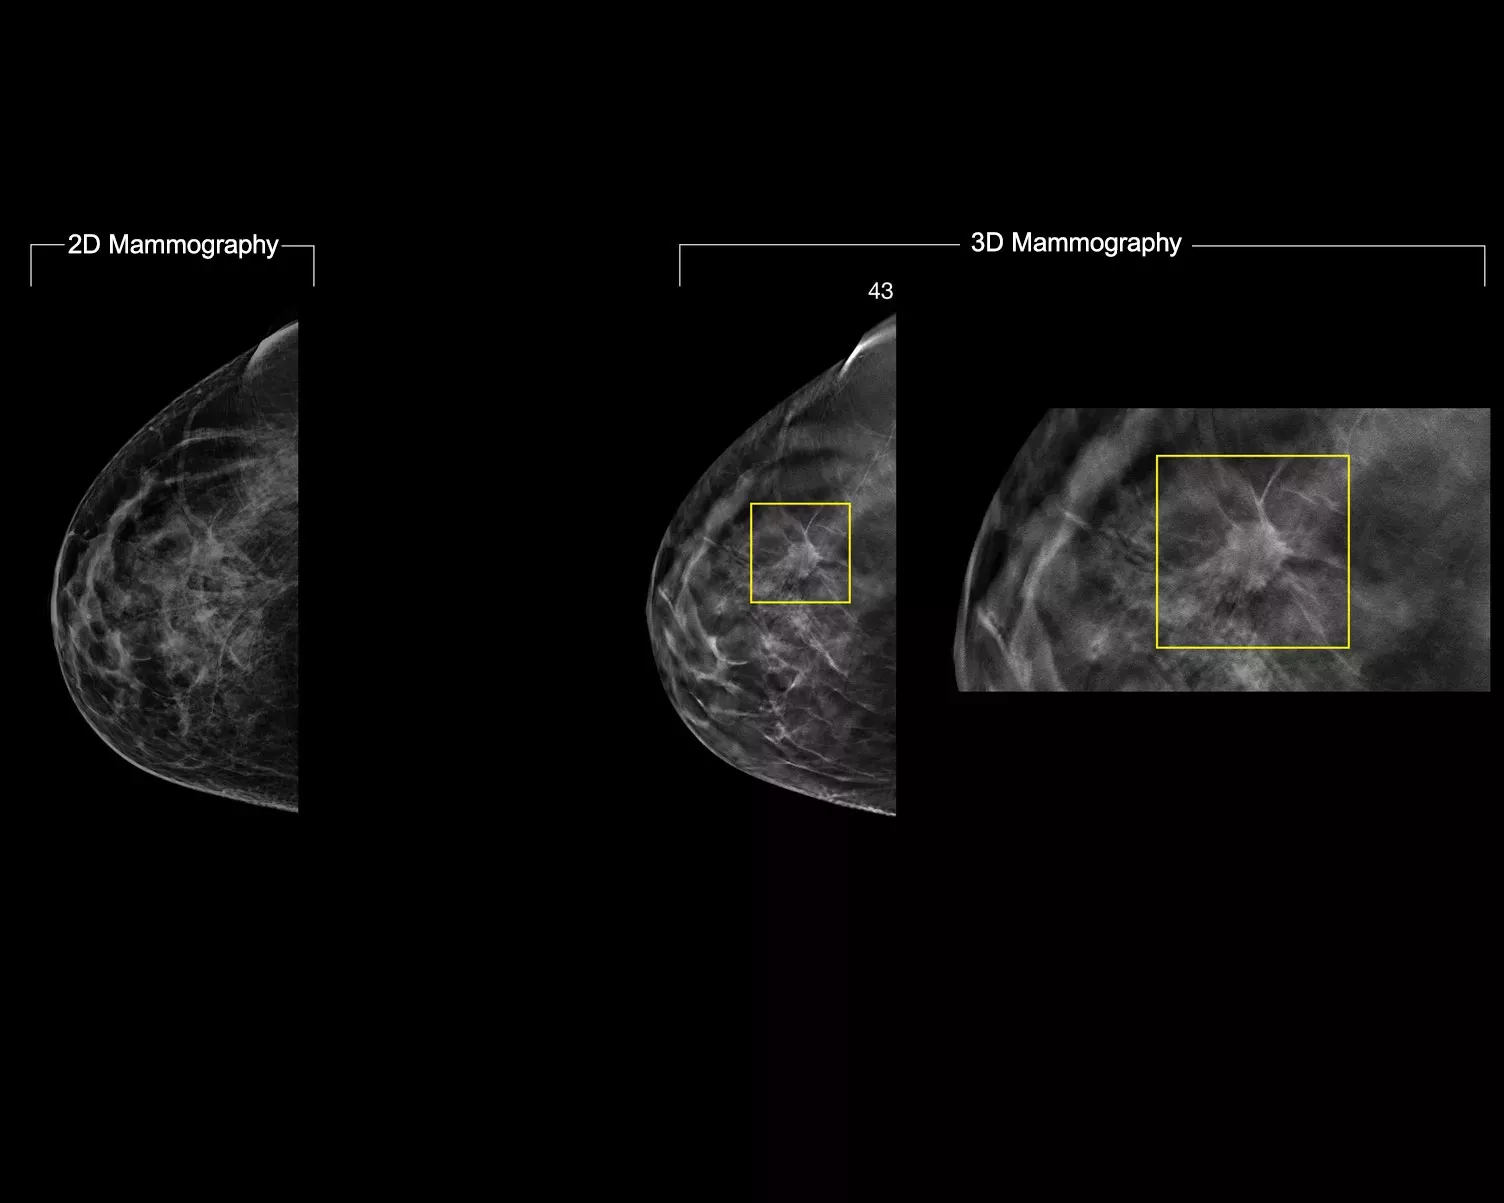

A deep-learning algorithm designed to aid radiologists' diagnostic performance of detecting breast cancer1-3 from tomosynthesis images obtained by using the Hologic Dimensions Mammography™ Systems. The algorithm locates lesions that are likely to represent breast cancer by searching each slice of the tomosynthesis image set. The suspicious areas are highlighted for concurrent reading at the radiologist's workstation to aid in interpretation.

The algorithm looks for 3 main groups of suspicious lesions: calcifications, masses, densities and distortions, and any combination of these lesions. Outputs may vary on different reading workstations.

AI Image Gallery